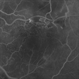

- Condition/keywords

- retinal ischemia

- This patient with long standing diabetes has peripheral non-perfusion.